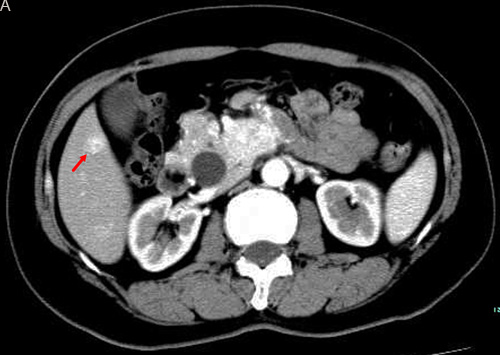

According to the imaging findings from before and after therapy, excluding the one case that was lost to follow-up, there were 11 PR cases (42.3%), 10 SD cases (38.5%), 5 PD cases (19.2%), and no CR cases. The efficacy rate was 42.3% (Figures 1 and 2).

Figure 1: TACE in a 59-year-old female with multiple liver metastases form pancreatic neuroendocrine tumor. A. Contrast-enhanced CT before TACE revealed a segment 6 hypovascular liver metastasis in the arterial phase (arrow) B. contrast-enhanced CT showed a significant decrease in the lesion at 6 months after treatment (arrow).